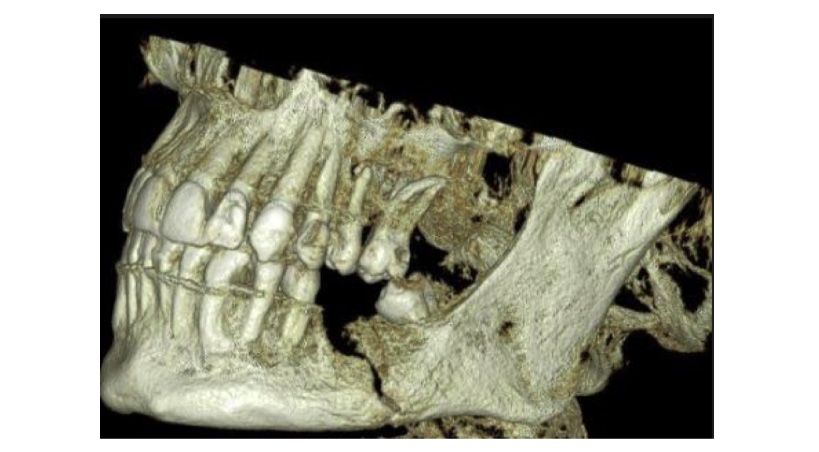

Condiciones de aplicación del injerto ilíaco óseo en la sustitución de defectos mandibulares

Un estudio retrospectivo de 11 años de experiencia